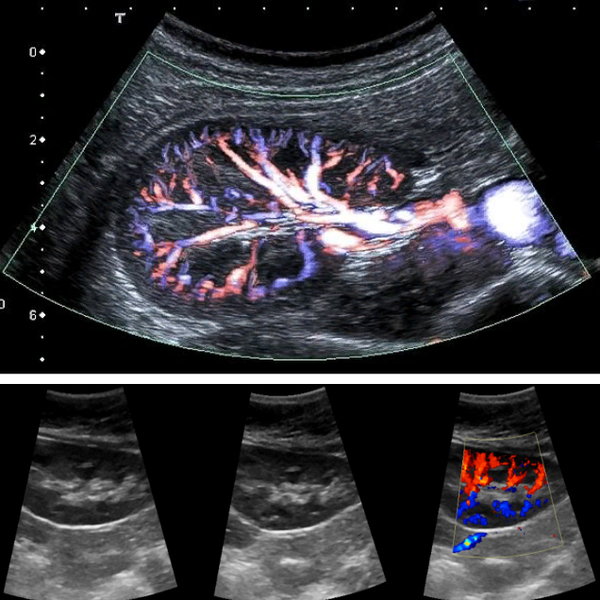

Оценить работу почек можно по биохимии крови. Однако, показатели могут быть разными в зависимости от проблемы. Для первичного приема нефролога достаточно сдать общий анализ мочи и составить историю из анализов мочи ( мочевой лист) , взять последний клинический анализ крови. У нас в медцентре также разработана программа обследования почек, которая включает базовые лабораторные показатели крови и мочи и дуплексное сканирование сосудов почек.